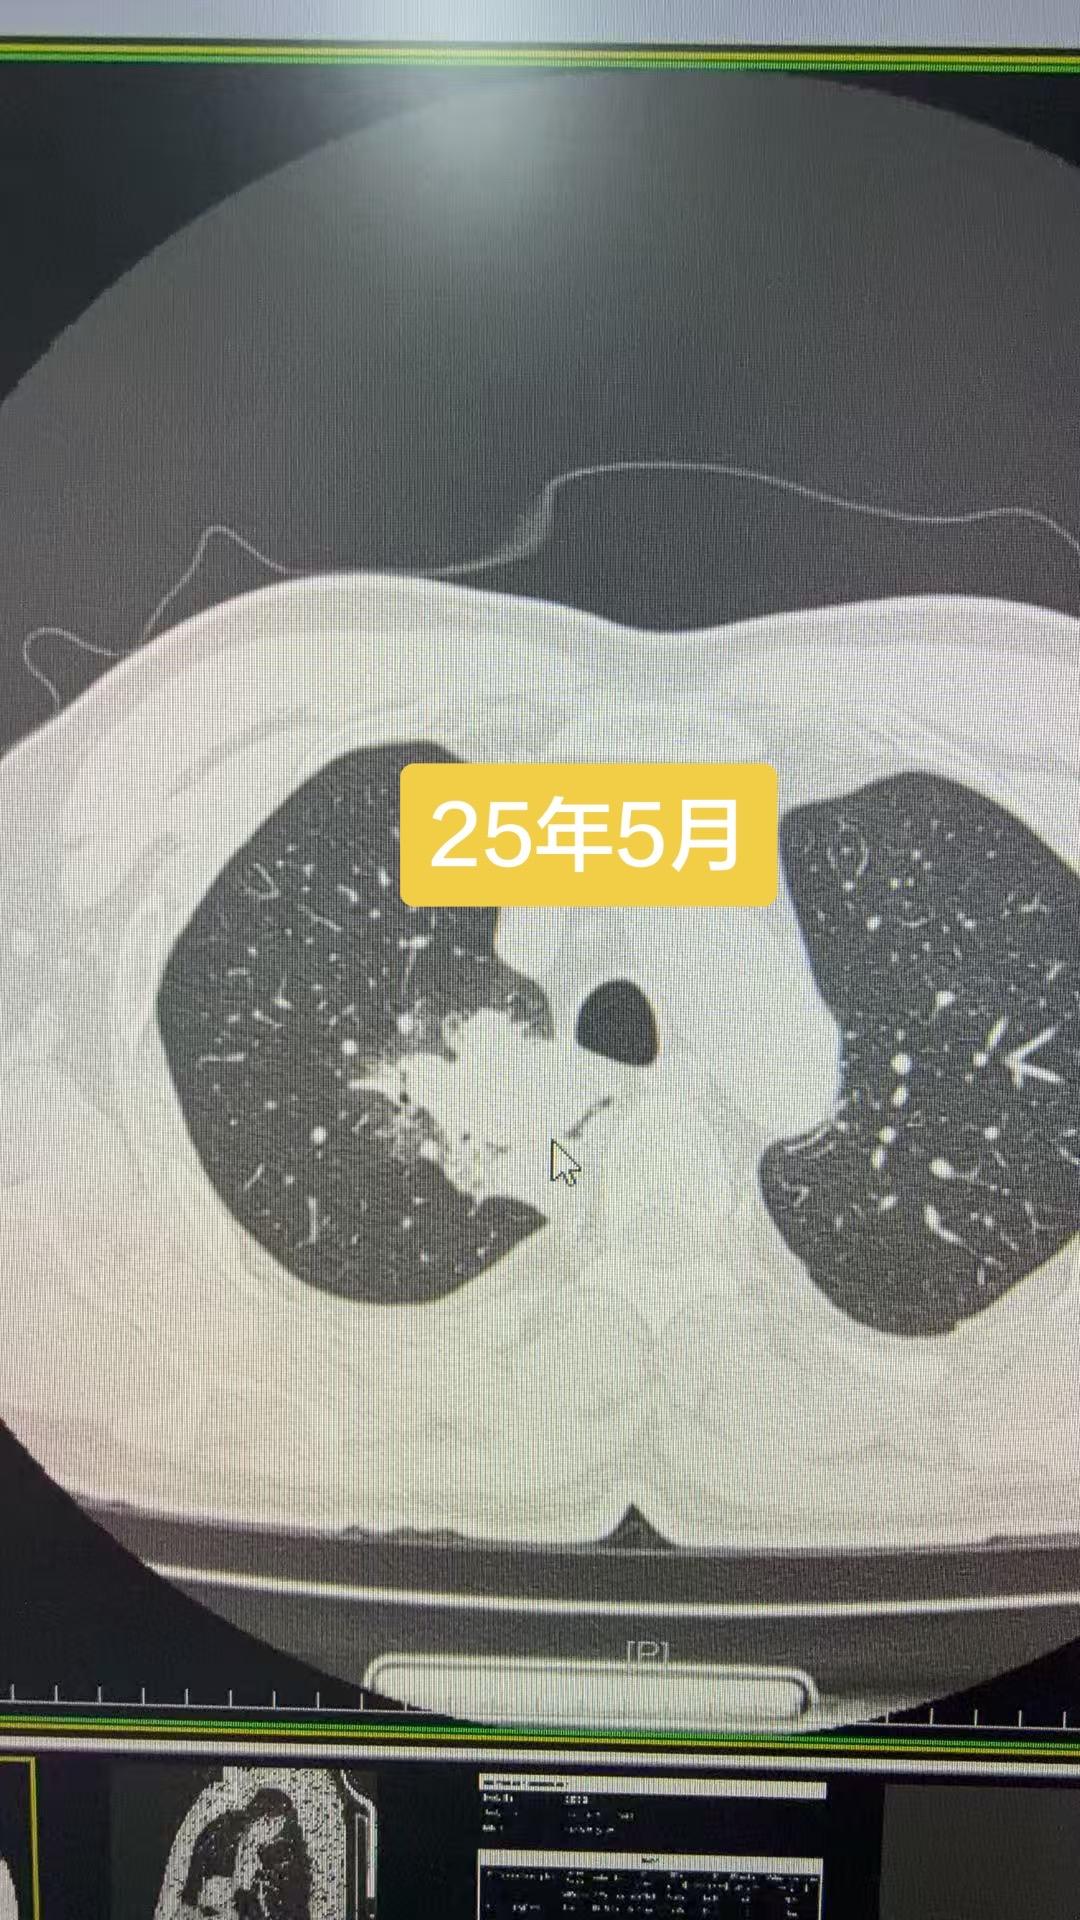

23年6月就发现的恶性结节,讳疾忌医,直接拖成晚期……猝于26年3月…...

23年6月就发现的恶性结节,讳疾忌医,直接拖成晚期……猝于26年3月……肺部结节虽然绝大多数是良性,持续增大的结节还是要重视,这个病人自己拖出大事……反面教材……